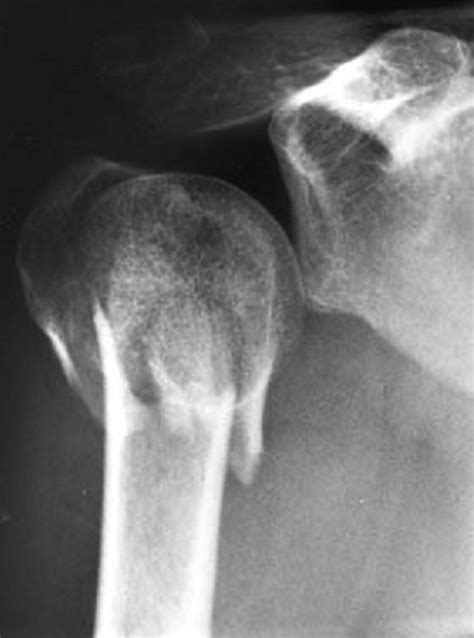

Diagnosis of Humerus Bone Head Fracture

Diagnosing a humerus bone head fracture involves a combination of physical examination and imaging tests. The diagnostic process typically includes:

• Physical Examination: The doctor will assess the shoulder for pain, swelling, and deformity.

• X-Rays: Standard imaging to visualize the fracture and determine its severity.

• CT Scan: For more detailed images, especially if the fracture is complex or involves the joint.

• MRI: To evaluate soft tissue damage and assess the extent of the injury.